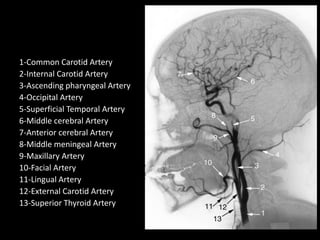

1-Common Carotid Artery

2-Internal Carotid Artery

3-Ascending pharyngeal Artery

4-Occipital Artery

5-Superficial Temporal Artery

6-Middle cerebral Artery

7-Anterior cerebral Artery

8-Middle meningeal Artery

9-Maxillary Artery

10-Facial Artery

11-Lingual Artery

12-External Carotid Artery

13-Superior Thyroid Artery